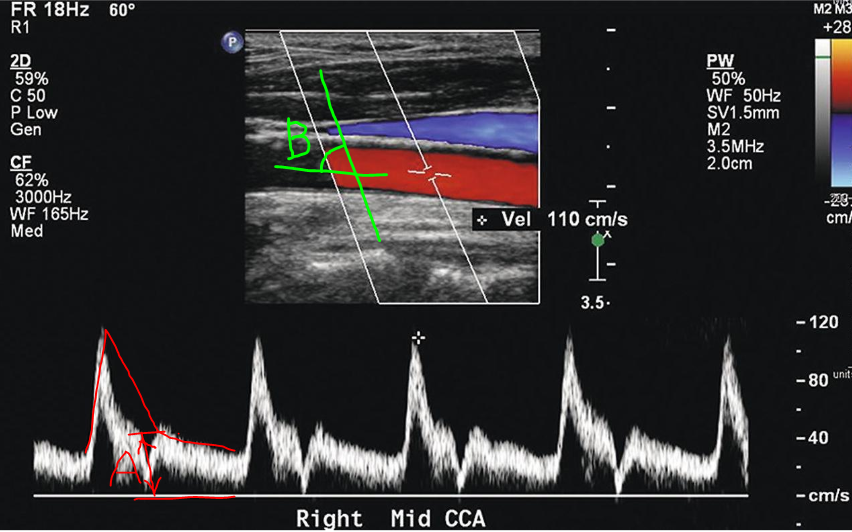

15. Rt. CCA waveform

14. Rt. CCA longitudinal view

waveform 측정시 B각도는 45도 정도가 적당하다. (초음파 장비의 steer와 angle로 조정)